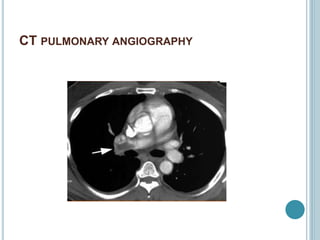

CT PULMONARY ANGIOGRAPHY

 It is investigation of choice